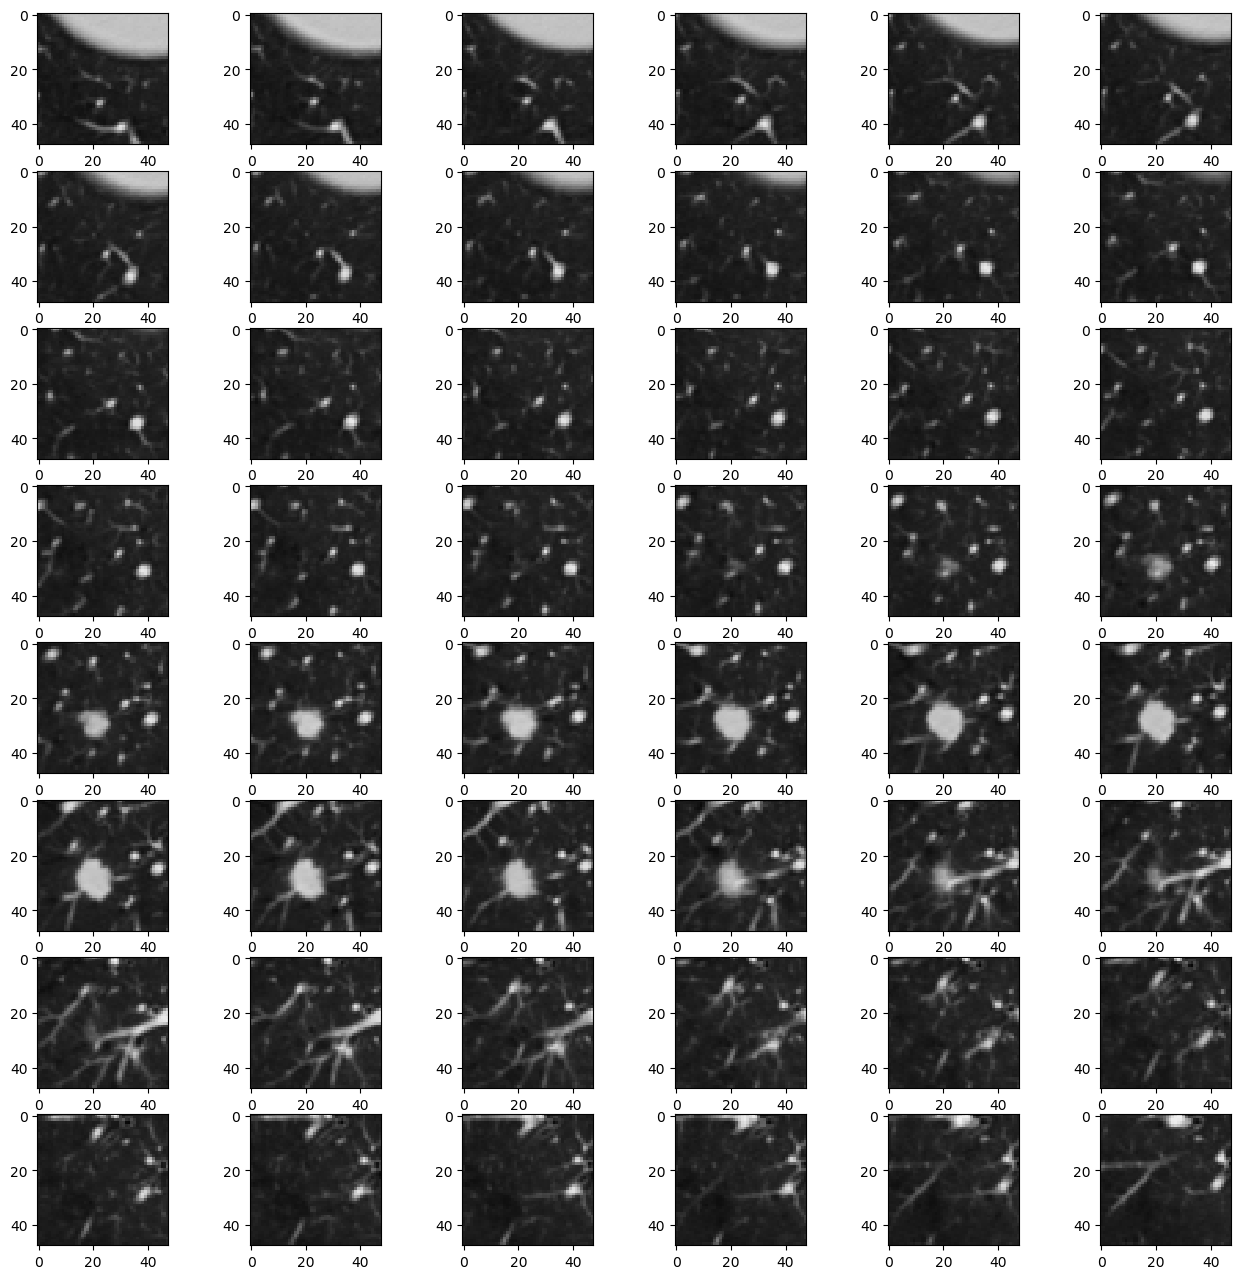

Refer to caption

Figure 7: predicted sample result.

The proposed 3D CNN architecture achieved an accuracy of 94.8% on validation data. Figure 3 shows the training accuracy and validation accuracy as the model was trained. It may be observed from the figure that the accuracy is gradually increasing during training. Figure 4 shows that the loss curve of training samples and validation samples.To improve the quality of this model, the validation loss and validation accuracy over epochs was monitored using tensorboard logs and hyper parameters were appropriately adjusted. The performance with respect to accuracy becomes stable after several iterations. This behavior is correlated with the change in loss as shown in Fig 5 which is decreasing gradually during training, and when the network obtains an optimal point then the training process becomes stable. Overall, the proposed deep 3D convolutional neural network is effective in classification as shown in fig 4 depicting the accuracy during the validation process. In order to demonstrate the performance of our model a complete CT scan containing annotated malignant nodule was sampled into multiple cubes using sliding window and subsequently fed to the trained 3D CNN network and probabilistic predictions corresponding to each input sample is plotted in 2 Dimension. Fig 6 shows the predicted probability map from the model in 2 Dimension while fig 7 shows the regions with probability greater than 90% after removal of noisy predictions .Fig 8 shows 2D slice of corresponding input sample. It may be observed that location of the annotated nodules has very high-probability but a small number of false positives are also predicted as shown in Fig 6. Evaluation of model on test data yielded a score .208 and accuracy of .9514.Due to the extensive duration of the training process hyper-parameters initial learning rate, momentum decay was adjusted only once. Further optimization of these parameters is expected to improve the quality of the model and reduce false positives.